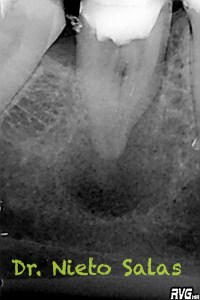

Usamos técnica de obturación por ola continua de Buchanan modificada y hacemos un backfilling con gutapercha inyectada.

Bueno, pues nos llegó hace unos meses a revisión después de 8 meses y a la paciente se le valoraba sin síntomas y con signos evidentes de evolución positiva.

Me gusta ser conservador con los diámetros apicales, para deformarlos lo menos posible. En este caso no fue así por la anatomía que presentaba, adapté bien los conos maestros con un diámetro más o menos 45 en el conducto distal(recuerda que era acintado con lo que no es posible un único cono apical) y 30 los mesiales.